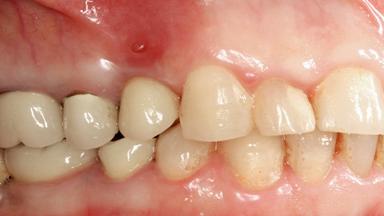

Excess Cement Resulting in Peri-implant Infection Presenting as a Draining Sinus Tract

Biological complications caused by undetected cement residue have been receiving much attention. Excess cement might be responsible not only for rapidly developing of peri-implantitis, but also for delayed or chronic manifestations of the disease many years after cementation (Wilson 2009; Linkevicius and coworkers 2013). Invitro and clinical studies have shown that it is very difficult or even impossible to completely clean up excess cement at subgingival margins, so popular in cemented restorations (Agar and coworkers 1997; Linkevicius and coworkers 2011, 2012). Possible outcomes of biological complications due to excess cement range from temporary inflammation of the peri-implant soft tissues without any serious esthetic and functional consequences all the way to implant loss. This report describes a case of peri-implantitis caused by residual cement; as well as the management and quite unusual resolution of the complication. The patient presented in 2009 with a draining sinus tract, tenderness on chewing, and tissue contact above the implant-supported restoration. The implant had been restored approximately three years before.